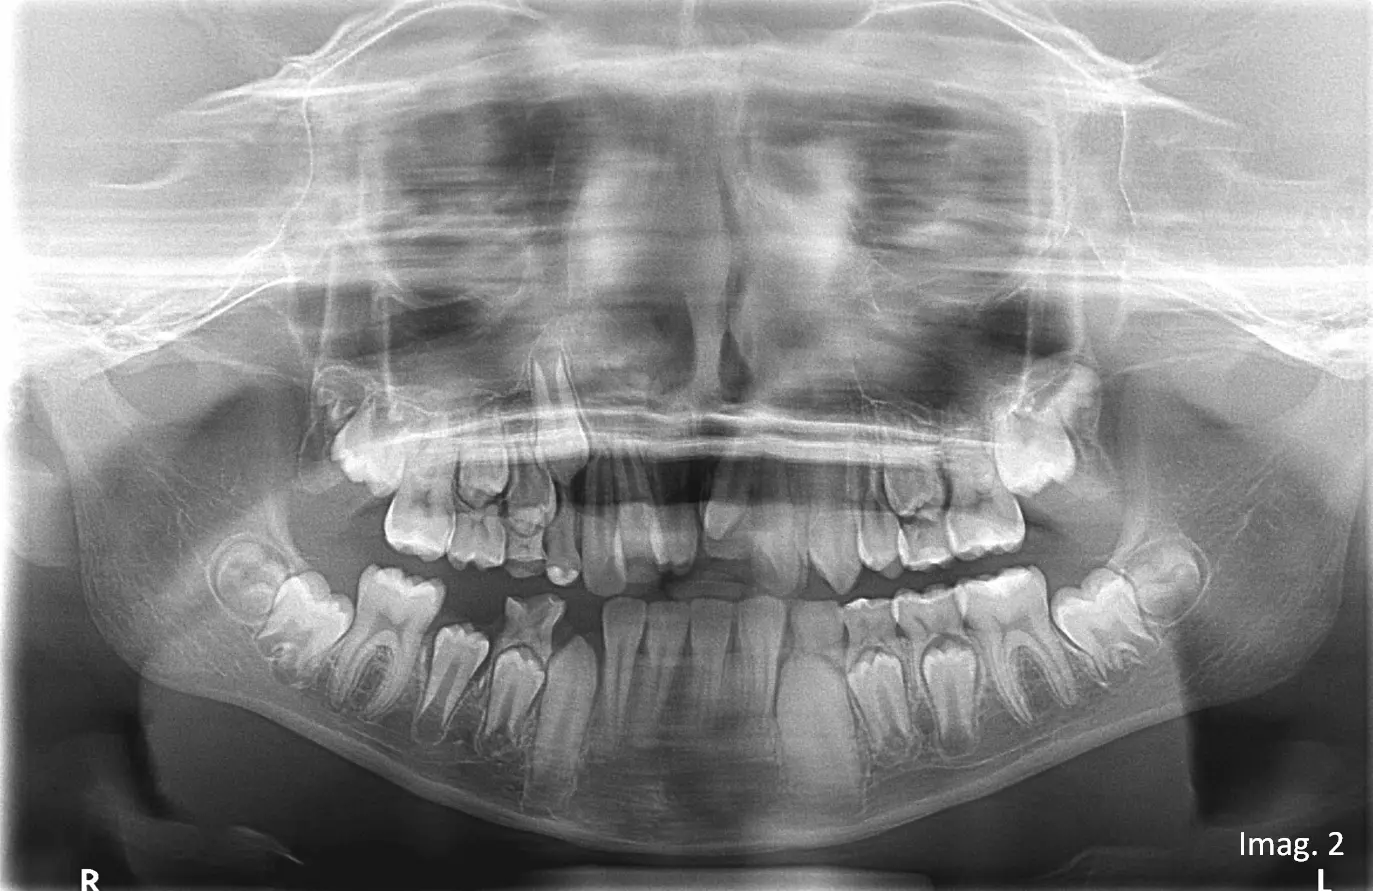

(Imagen 2). Dada la limitación inherente del estudio bidimensional para determinar con exactitud la posición vestíbulo-palatina, la orientación tridimensional y la posible presencia de piezas adicionales, se indica estudio tomográfico.

En el estudio tridimensional se confirma la presencia del Mesiodens clínicamente observable y además se identifica un segundo Mesiodens incluido, no detectable en el estudio panorámico inicial (ver imagen 3, vista axial).